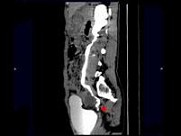

- 多项选择题女,42岁, 左侧腰背部胀痛不适1年余,5年前行左侧卵巢囊肿切除术, CT检查如图所示,下列说法正确的是 ( )

A、左侧附件区可见一囊性肿物,压迫输尿管下段

B、左侧输尿管下端狭窄

C、左侧肾盂肾盏扩张积水

D、左侧输尿管中上段扩张

E、考虑为左侧卵巢囊肿术后复发压迫并粘连输尿管致其狭窄